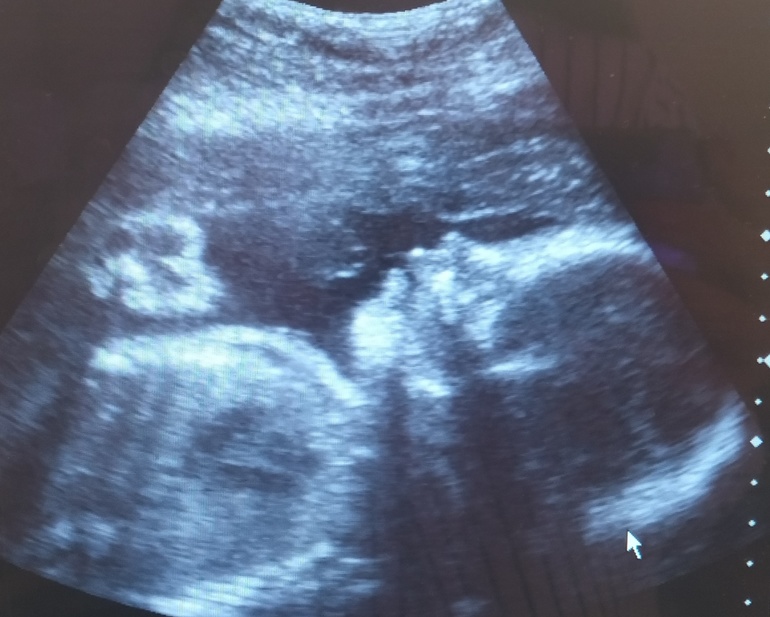

Ну и фото этого сладкого карапузьона😍

Мне кажется, что на меня похожа😀💪